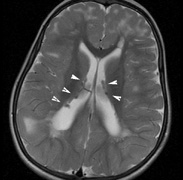

Mental retardation and seizures in TSC are often associated with benign CNS astrocytic hamartomas.131 On imaging, the cerebral lesions show three patterns:132

1. Superficial cortical sclerosis (parenchymal hamartoma) which distort the gyri. Microscopy shows large atypical fibrillary type astrocytes with few associated neurons and areas of calcification.133 The numerous abnormal glial processes and fibers make the tissue abnormally firm or “sclerotic” on palpation (Fig. 13).132

2. Subependymal nodules (SEN) are typically found along the lateral borders of the ventricles and parehncymal brain lesion (“cortical tubers”) (Figs. 14 and 15). Calcification in the first year of life is rare.132

3. White matter abnormalities are a characteristic “ventriculofugal” pattern corresponding to the embryological migratory paths of neurons and glia. These lesions may represent aberrant neuronal migration, a possible reflection of haploinsufficiency for the TSC gene.116,132,134

On MRI imaging, the subependymal nodules and parenchymal brain lesions of infants (age ≤3 months) and adults show different signal characteristics. Infant CNS tubers are hyperintense on T1-weighted images and hypointense on T2-weighted images, which is the opposite of the pattern seen in adults.134 Malignant transformation of SEN occurs in about 10% to 15% of patients and the resultant subependymal giant cell astrocytoma accounts for 25% of premature deaths in TSC.135,136

Fig. 15. Tuberous Sclerosis Complex. (a) Patient 1: Axial CT scans demonstrating typical calcification of subependymal nodules in a 13-year-old girl with a history of seizures. (b and c) Patient 2. (b) Axial T2-weighted images demonstrate calcified subependymal nodules (arrowheads) and cortical tubers typical of tuberous sclerosis. (c) Widespread cortical tubers are seen on a coronal FLAIR sequence as thickening of the cortex and high signal of the subcortical white matter.